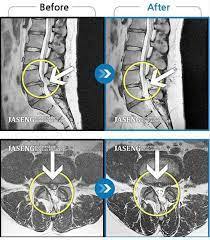

ヘルニアなどが分かりやすいですが、飛び出している椎間板が神経を圧迫して痛みや痺れを出していますので、その飛び出している部分を切除すれば痛み・痺れはウソのように消えてしまうことがほとんどです。

手術となると、不安でなかなか踏み切れない方も多いですが、最近では内視鏡による日帰り手術が主流になっているので、身体の負担も少なく、受けれるようになっていますので、長引いている方は是非、病院で納得いくまで話を聞いて、前向きにやってみようと思われるのであれば治療の選択肢の1つとして考えるのもアリだと思います。